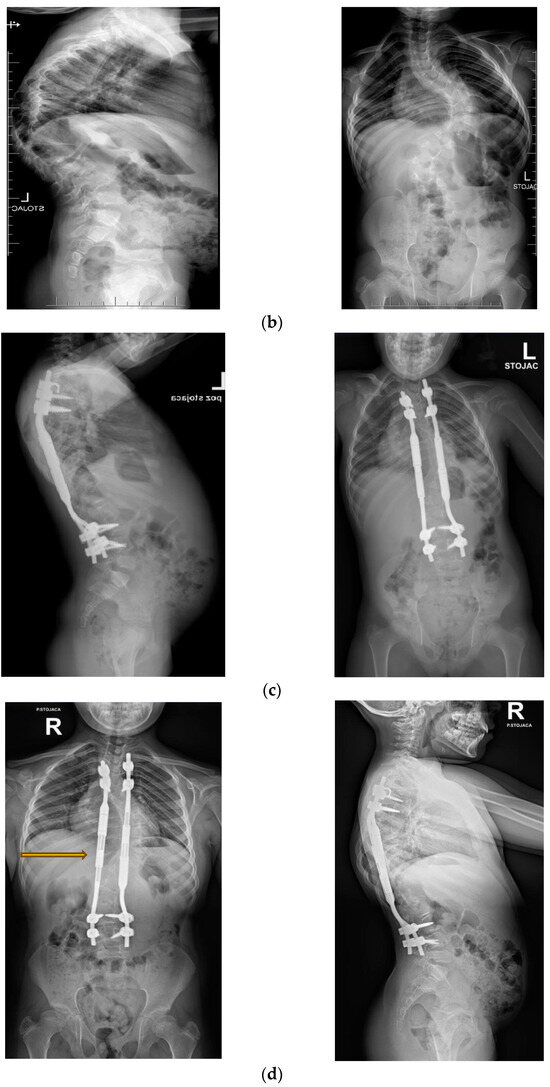

2.3. Surgical Technique and Postoperative Use of MCGRs